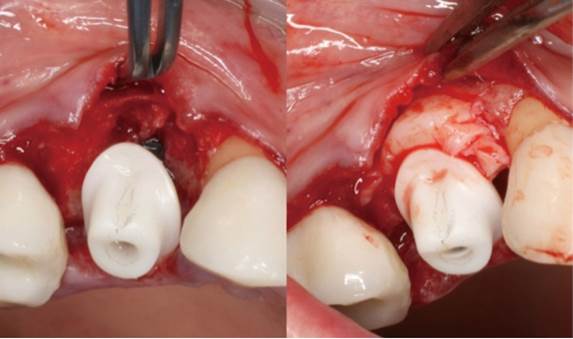

Clinical case: Extraction, immediate implant placement, & provisionalization

- Courtesy of Dr. Iulian Filipov, Romania -

Keywords

AnyRidge, R2GATE, guided surgery, immediate placement, immediate provisionalization, initial stability, Dr. Iulian Filipov, #25, maxillary posterior, immediate loading, Mega ISQ

Products:

AnyRidge implant system, R2GATE, MEGA ISQ, Digital prosthesis